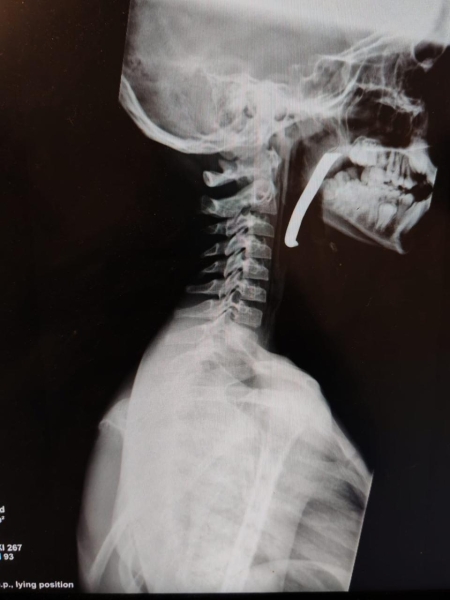

الوقائع الاخبارية:أجرت طواقم المستشفى الميداني الأردني جنوب غزة/6، أمس الأحد، عملية جراحية ناجحة لإنقاذ حياة طفل، تم خلالها استخراج شظية كبيرة الحجم اخترقت الرقبة والبلعوم والمجرى التنفسي، وذلك من خلال استكشاف جراحي دقيق للرقبة.

وأوضح مدير المستشفى أن الطفل كان يعاني من إصابة بالغة على مستوى الرقبة والبلعوم، حيث اخترقت الشظية مناطق حيوية وأدت إلى صعوبة في التنفس، مما شكل تهديداً مباشراً لحياته. وأضاف أن الحالة كانت حرجة، وتطلبت تدخلاً جراحياً فورياً نفذه فريق طبي متخصص يضم أطباء في الجراحة العامة، والتخدير والإنعاش، وجراحة الأطفال، وجراحة الأنف والأذن والحنجرة، وبمتابعة دقيقة من الأطباء المختصين، وتم استخراج الشظية بنجاح عن طريق الفم، وحالة الطفل الآن مستقرة.